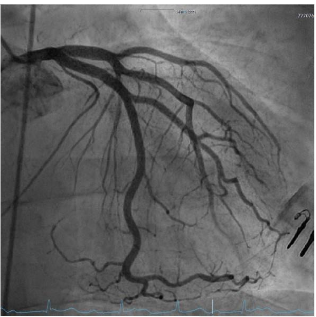

A 27-year-old patient presented with suspected ST-segment elevation myocardial infarction (STEMI). Approximately one hour prior to admission, the patient experienced onset of typical angina pectoris with accompanying vegetative symptoms (nausea and vomiting). Similar episodes had not occurred before. The patient’s medical history revealed regular or daily consumption of high-percentage alcohol, nicotine and cannabis. A few days before the event, the patient intended to consume nasal amphetamines, but due to a mix-up the substance consumed was heroin. No further substance use was reported. Furthermore, the patient had a tick bite approximately 10 years ago. The initial electrocardiogram (ECG) showed ST segment elevations in leads II, III, and avF, as well as a second-degree atrioventricular block (Mobitz type II) with a heart rate of approximately 70 beats/minute. Laboratory tests showed elevated cardiac biomarkers, with (troponin I 14.037 µg/l (cut-off value <0.045 µg/l) and CK-MB at 79 U/l (cut-off value <24U/l). Furthermore, the patient exhibited a flamboyant exanthema in large areas of the face with known atopic dermatitis. The patient reported of a pronounced stress response triggered by various problems in the work environment and social circle. After findings were reviewed in the Chest Pain Unit, based on the initial assessment, the patient was immediately transferred to the catheterization lab. The attending physician administered prehospital medication with aspirin and heparin. An emergency coronary angiography was performed, which revealed a single-vessel coronary disease with a subtotal occlusion of the right coronary artery (RCA) and high thrombus burden. During the procedure, the patient admitted that he had smoked marijuana the same morning. A primary stenting using a drug eluting stent (DES, Promus 4.0/32mm, Boston Scientific, Marlborough, Massachusetts) was performed, followed by stent optimization with balloon angioplasty. Complete reperfusion was documented immediately without evidence of remaining dissection or vascular injury. The placement of a temporary pacemaker was not necessary and the patient was transferred to our intensive care unit. Post-interventional follow-up showed no evidence of atrioventricular block and complete ST resolution on the following day. Dual antiplatelet therapy with acetylsalicylic acid and ticagrelor was initiated. On the following day, there was a slight increase in troponin I to a maximum of 18.469 µg/l, after which it then decreased, similarly CK values decreased. In addition, there was a slight increase in inflammatory markers, (CRP 41 mg/l, leukocytes 14.000/µl). LDL cholesterol was significantly elevated at 150 mg/dl (fasting, the following day), while HDL cholesterol was within the normal range at 40 mg/dl and triglycerides were at 145 mg/dl, Lipoprotein (a) 6.3 mg/dl. The urinary toxicology test showed a qualitative detection of benzodiazepines, cannabinoids, and opioids. Interestingly, serologically, IgM antibodies against Borrelia burgdorferi were detected without IgG antibodies. Further diagnostic workup included transthoracic and transesophageal echocardiography, which showed a severely reduced left ventricular ejection fraction (LVEF) of 29% by Simpson (biplane analysis), as well as an inferior inferolateral akinesia. Additionally, a floating structure measuring approximately 8x8mm was observed attached to the inferolateral wall, suggesting a ventricular thrombus. To further confirm the diagnosis and investigate the reduced LVEF, a cardiac magnetic resonance imaging (MRI) was scheduled. The possibility of providing a life vest was discussed until a decision regarding an implantable cardioverter-defibrillator (ICD) was made. Unfortunately, the patient declined further tests and treatments and left the hospital against our advice.